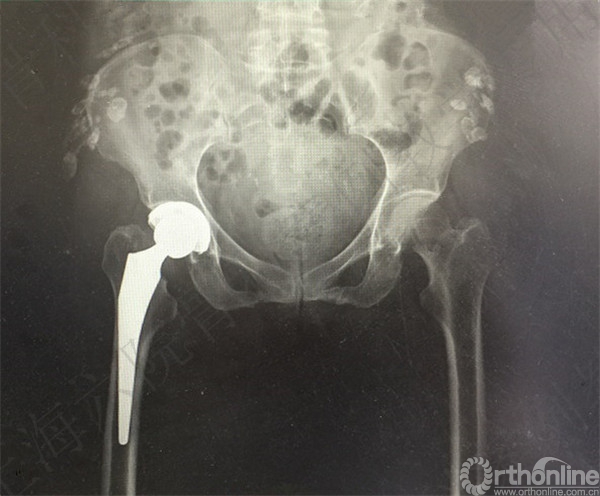

急诊予全麻下手法复位。

X线摄片示:右髋假体复位,骨折对位对线可,假体无明显松动。

嘱患者患肢丁字鞋固定,卧床制动6周。